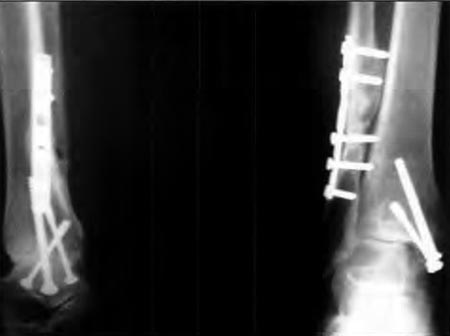

La causa más frecuente de artrosis fue la postraumática (diez casos).(Fig. 1) Otras etiologías fueron Artritis Reumatoidea en dos casos, artropatía hemofílica dos tobillos en un paciente, secuela de poliomielitis un caso, osteocondrítis de astrágalo un caso.

Figura 1 a: Rx de tobillo con osteosíntesis

Figura 1 b: artrosis secundaria 2 años después